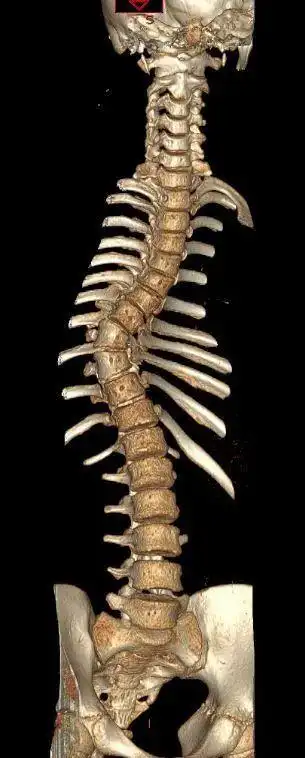

由于脊柱侧弯扭转严重,腰椎变形移位,患者无法配合完成常规的腰穿体位

郑骨医,小儿骨科二脊柱侧弯科短阶段固定治疗脊柱侧弯一例